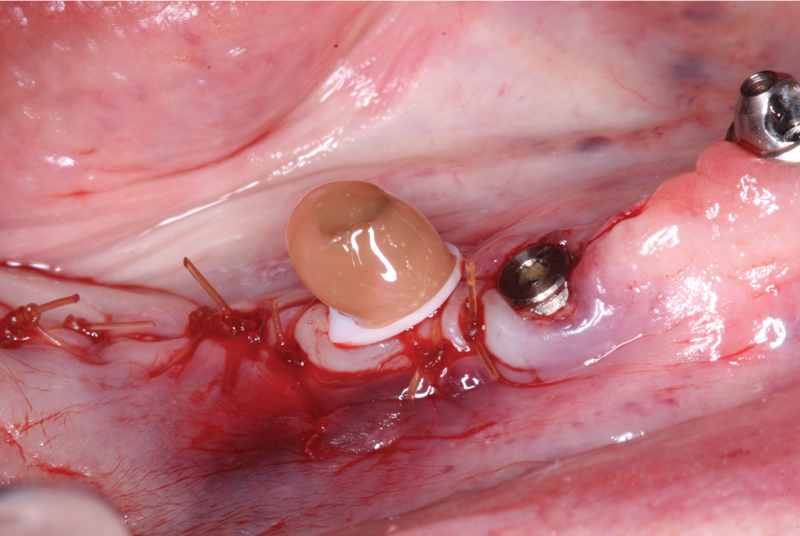

The spherical abutment of the appropriate cuff height was selected and torqued into place using a dedicated abutment driver (Figure 15). Considering the need to immediately retrofit the patient's PMMA screw-retained bridge, as well as anticipate retrofitting the already fabricated full zirconia prosthesis, using an abutment with a spherical geometry that enables the denture attachment housing to pivot in any direction would be significant to ensuring a stress-free, passive fit and proper prosthesis alignment.17,18

After achieving primary closure with a 4.0 chrome gut suture (Figure 16), a denture attachment housing and white spacer were placed onto the LOCATOR F-Tx abutment and pivoted into the correct orientation (Figure 17), creating an easily drawn path of insertion and removal for the PMMA prosthesis. To limit vertical and rotational movement, contribute to stability, and lock the prosthesis into place, the denture attachment housing features grooves and flats that ensure the housings remain locked into place within the prosthesis. Internally threaded to accept polyether ether ketone (PEEK) retention balls and a processing ball that snaps into the abutment, the attachment housing eliminates otherwise intensive chairside procedures to retain the screw-retained prosthesis.

Fig 15. The LOCATOR F-Tx abutment was torqued into place.

Figure 15

Fig 16. Primary closure was achieved using a 4.0 chrome gut suture.

Figure 16